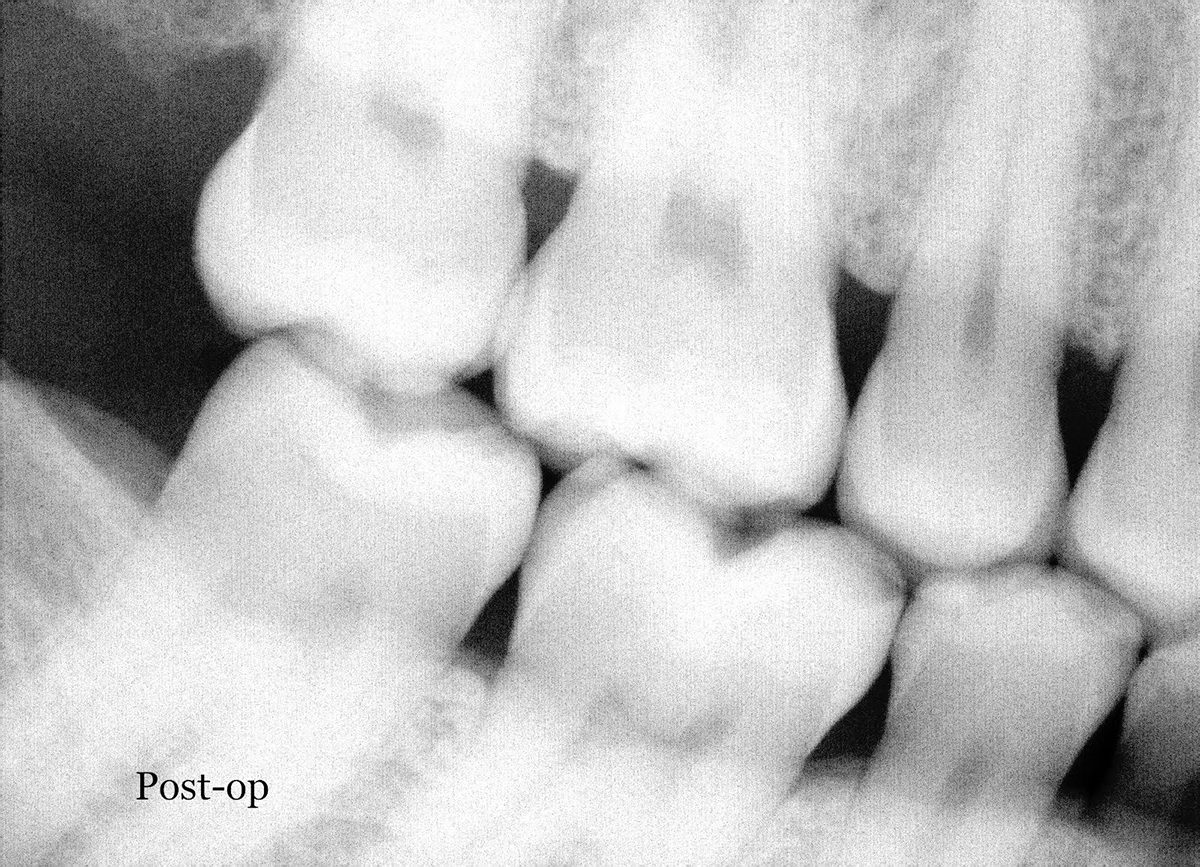

After 2 weeks, the crown was back from the laboratory. The temporary was removed, the crown was placed on the tooth, the interproximal contacts were checked with dental floss, and the occlusion was examined. Before the final cementation, a bitewing x-ray was taken to confirm the seal of the mesial and distal margins. After the seal was confirmed, the tooth was isolated with cotton rolls, and universal bond was prepared, applied to the crown (Figure 12) and tooth (Figure 13), and lightly air-dried. Cement was placed on the crown, and the crown was then placed on the tooth (Figure 14). Figure 15 shows the crown after the final cementation. The cement and universal bond pairing allowed for self-etch adhesion and required no additional activators or primers.

Fig 7. Six-month recall x-ray of restoration.

Figure 7

Fig 14. The crown was placed on the tooth.

Figure 14

Fig 15. Postoperative photograph of the crown after the final cementation.

Figure 15